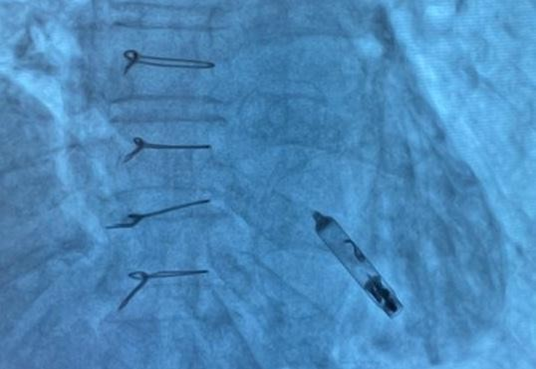

Under fluoroscopic guidance, the delivery catheter was advanced through the right atrium. Significant resistance was encountered as the catheter tip repeatedly abutted the ventricular wall due to the limited chamber size. To overcome this, the catheter was reshaped into a “hockey-stick” configuration developed by our team (Fig. 4–9). This modification enabled safe passage through the tricuspid valve and facilitated navigation to the apical-septal region. Contact mapping confirmed optimal electrical parameters before fixation, and the device was screwed into the septum. Device interrogation demonstrated proper function: pacing threshold 0.75 V at 0.4 ms, R- wave amplitude 6.0 mV, impedance 750 Ω, mode VVI, with estimated battery longevity of ~12 years.

Figure 7. Final position of the leadless pacemaker inside the small right ventricle

Immediate device interrogation confirmed stable electrical performance: pacing threshold 0.75 V at 0.4 ms, R-wave 6.0 mV, impedance 750 Ω, estimated longevity ~12 years. At 6 months, follow-up showed: R- wave 6.2 mV, threshold 0.75 V, impedance 720 Ω, projected longevity 12 years. No complications were